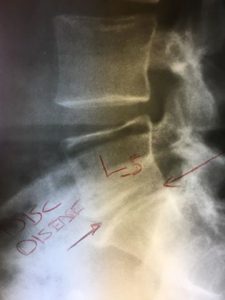

After 2 years of #Chiropractic corrective care we have been able to regenerate Isabellas degenerative L5 intervertebral disc disease. The human body can overcome extreme health obstacles if you just remove the interference and put the necessary time in.